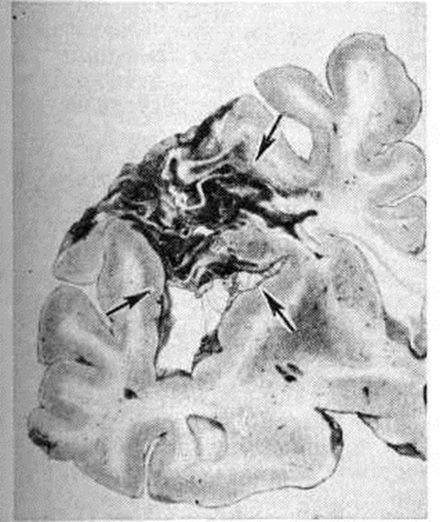

Геморрагический инсульт, как правило, возникает при заболеваниях, протекающих с повышенным артериальное давление. Это обусловлено тем, что сосудистые кризы (смотри полный свод знаний), характерные для гипертонической болезни (смотри полный свод знаний) и артериальной гипертензии (смотри полный свод знаний Гипертензия артериальная), приводят к морфологический изменениям стенок внутримозговых сосудов с нарушением их проницаемости — плазматическому пропитыванию (рисунок 1), некрозам (рисунок 2), образованию микроаневризм (рисунок 3) и их разрывам. Разрыв врождённых артериальных и артериовенозных аневризм может протекать на фоне нормального давления. Преимущественная локализация и характер геморрагий определяются особенностями ангиоархитектоники различных отделов мозга. При гипертонической болезни наиболее тяжёлым изменениям подвергаются сосуды подкорковых узлов и зрительного бугра. Это объясняется отхождением глубоких ветвей под прямым углом от средней мозговой артерии, являющейся продолжением внутренней сонной артерии, и незначительным числом анастомозов сосудов в этой области. В связи с этим на вскрытии кровоизлияния наиболее часто (40%) обнаруживаются в подкорковых узлах с распространением в прилежащее белое вещество (так называемый латеральные кровоизлияния, то есть расположенные латерально от внутренней капсулы, рисунок 4). Второе место по частоте (16%) занимают обширные кровоизлияния, разрушающие подкорковые узлы, внутреннюю капсулу, зрительный бугор (так называемый смешанные кровоизлияния — рисунок 5). Кровоизлияния в зрительный бугор (так называемый медиальные — рисунок 6) составляют 10%, в мозжечок — 6—10%, в мост мозга — 5% от общего числа внутримозговых геморрагий. Кровоизлияния только в белое вещество полушарий мозга встречаются крайне редко. Подразделение полушарных кровоизлияний на латеральные, медиальные и смешанные имеет особое значение в связи с хирургическим лечением геморрагического Инсульт.

Кровоизлияния типа гематомы сопровождаются образованием полости, содержащей жидкую кровь или свёртки крови; они составляют 85% внутримозговых кровоизлияний, наиболее часто развиваются в подкорковых узлах, реже в мозжечке. Основной механизм развития гематомы — разрыв патологически изменённого сосуда (рисунок 7). Формирование гематомы идёт путём раздвигания кровью вещества мозга с перемещением его участков, что возможно благодаря резервным пространствам (желудочки, подпаутинное пространство). Размеры гематомы при этом превышают объем разрушенного кровью вещества, сдавление окружающих отделов незначительно; лишь при кровоизлиянии в мозжечок сдавление вещества мозга весьма существенно в связи с анатомическими особенностями задней черепной ямки (рисунок 8).

Кровоизлияния типа геморрагического пропитывания возникают преимущественно в зрительных буграх, реже в мосту мозга и составляют 15% внутримозговых кровоизлияний. Они являются результатом слияния мелких очагов кровоизлияний, возникающих путём диапедеза из мелких сосудов, имеют вид очагов красного цвета, дряблой консистенции и в силу внешнего сходства иногда напоминают геморрагический инфаркт. В первые часы Инсульт нарушается проницаемость сосудов на границе с кровоизлиянием, развивается отёк; кровь распространяется по ходу нервных волокон. К концу первых суток наблюдаются лейкостазы и лейкодиапедез, размеры очага увеличиваются за счёт диапедезных геморрагий и некробиотических изменений в отёчном веществе мозга. Через двое суток начинается процесс репарации — появление зернистых шаров и гипертрофированных астроцитов; позже образуется вал из астроглии и новообразованных сосудов, кровь подвергается гемолизу, появляются макрофаги с гемосидерином, образуются аргирофильные и коллагеновые волокна. Исходом кровоизлияния может быть формирование глиомезодермального рубца или кисты, содержащих гемосидерин (рисунок 9). В 80—85% кровоизлияний на вскрытии выявляется прорыв крови в желудочки, значительно реже — в подпаутинное пространство. В последнее кровь может также проникнуть из четвёртого желудочка. Первичные вентрикулярные геморрагии нетравматического генеза — явление казуистическое. При разрыве врождённых аневризм артерий основания мозга возникают первичные субарахноидальные кровоизлияния, которые обычно локализуются на базальной поверхности или в латеральной борозде; иногда кровь проникает в субдуральное пространство; часто повреждается вещество мозга (субарахноидально-паренхиматозные кровоизлияния). Расположение гематом, образующихся при этом, зависит от локализации аневризмы, обычно это базальный отдел лобной доли или височная область. В части случаев при незначительном субарахноидально-паренхиматозном кровоизлиянии возможен массивный прорыв крови в желудочки (рисунок 10), что иногда ошибочно диагностируется как первичное вентрикулярное кровоизлияние.